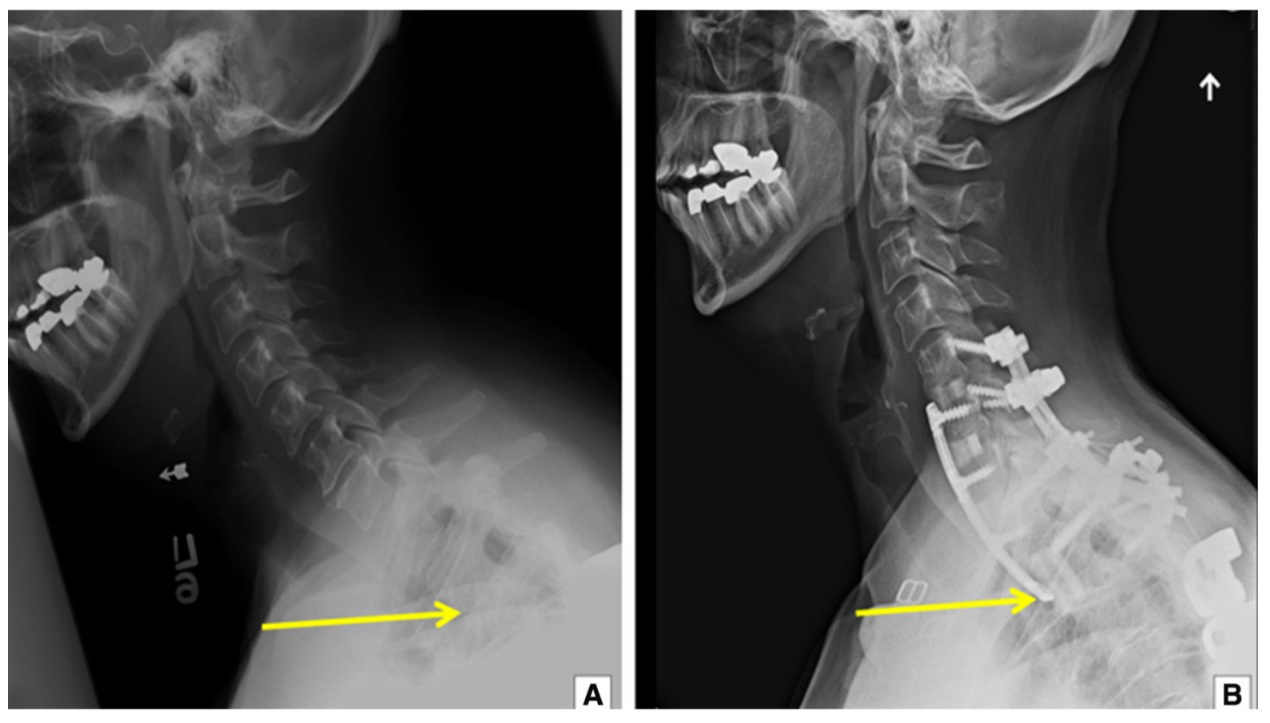

低头玩手机脑子竟然漏水了

1:正位片,图2-2:侧位片);ct显示上胸段角状后凸,t4-6椎体融合(图2-3)

胸椎脊柱肿瘤切除案例 后路钉棒 椎体切除 钛笼植入 - 好大夫在线

前沿|标准前方smith-robinson胸骨柄上入路是否可以向下显露到t2或t3?

上图:手术后:通过截骨切除半椎体,钉棒系统矫形固定,侧弯获得完全矫正